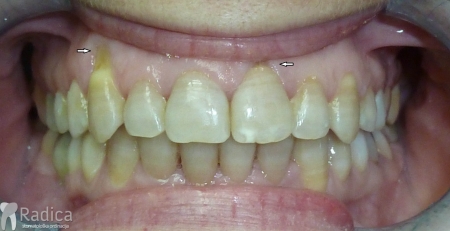

U galeriji slika su prikazani klinički slučajevi ovakvih odraslih pacijenta bilo da se radi samo o ortodontskoj terapiji ili predprotetskoj ortodonciji.

Kompresija –fiksni aparat bez ekstrakcije zuba

Slučaj 1